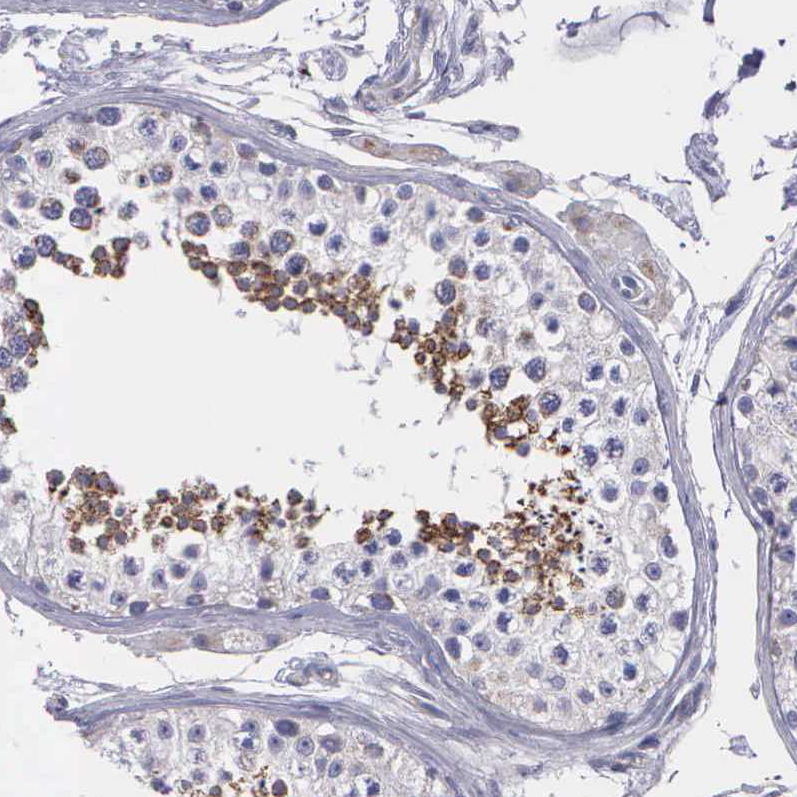

Immunohistochemical staining of human duodenum shows strong granular cytoplasmic positivity in glandular cells.